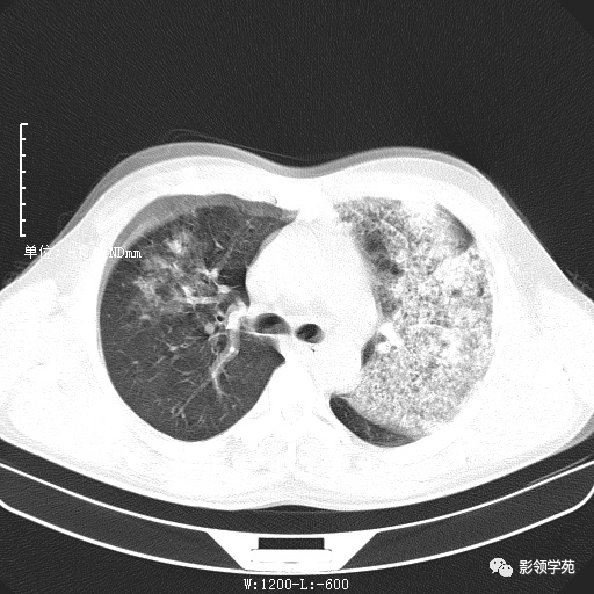

唐绍宏老师探索军团菌肺炎影像表现多图示

图片尺寸960x720